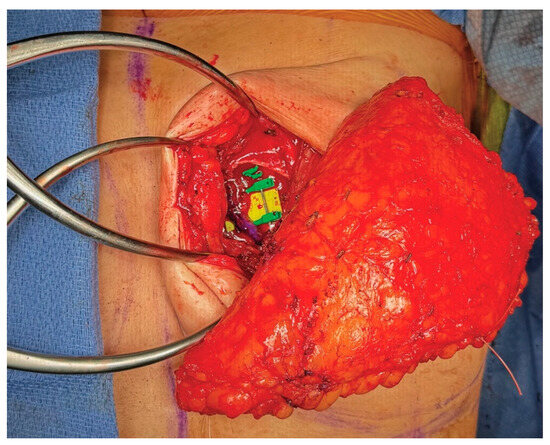

3.4. Operative Technique

4.4. Operative Technique